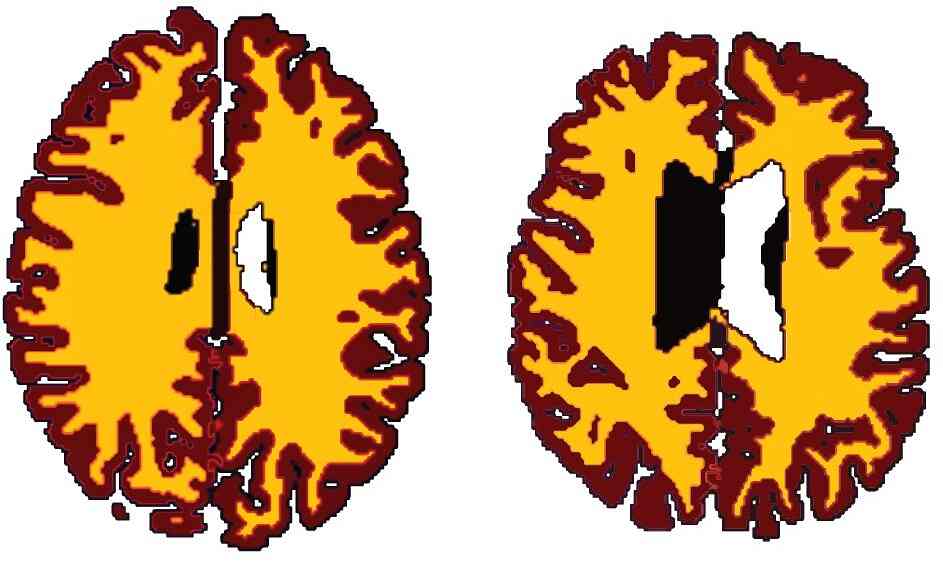

Não bộ người bình thường (trái) và người béo phì (phải)

Sau khi so sánh, họ nhận thấy những người thừa cân có bộ não già hơn người thường cả chục tuổi. Tức là một người 50 tuổi bị béo phì có lượng chất trắng ngang với người 60 tuổi nhưng có cơ thể bình thường.